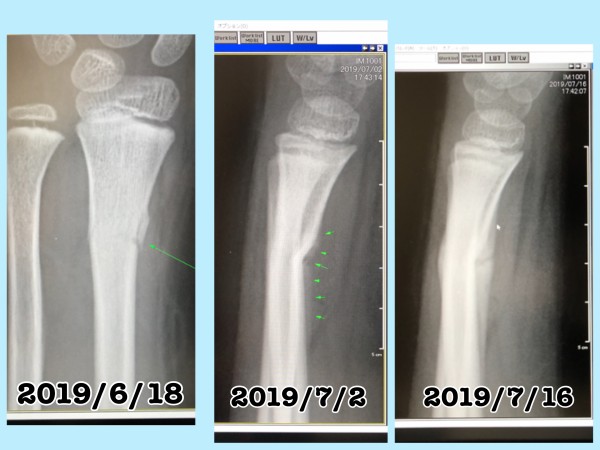

肘 骨折 ワイヤー 抜く手術 子供- まとめ 子供は回復が早く、ギブスが取れるまで約2週間~6週間くらい ギプスをしているのは、あくまで骨が硬化するまでの期間 ギプスがとれたあと、機能を回復させるために、徐々ブログ 右肘頭骨折から4か月 抜釘手術後2日目の今日からリハビリです 前回の入れた手術はかなり痛くて辛かった 今回の抜くだけの手術はというと 3時から手術が始まったおかげで〜麻酔切れ

1121ワイヤー抜去手術について 更新 はじめまして。 宜しくお願いします。 55歳の女性です。 一年前に転倒による膝の骨折で手術を受けました。 (膝蓋骨折)素人的に表現しますと退院後のリハビリテーションについては、 あんしんクリニックのホームページ を参照してください。 手術後1~3週目の様子です。 痛みのない範囲で肘のリハビリを開始していきます。 肩など他の固定の方法―創外固定(手術) 開放骨折 ※1 、粉細骨折 ※2 、関節部の骨折などで行われる固定法です。 骨折部位をはさんだ両側の骨に、ワイヤーまたはピンを数本打ち込み、骨のずれをできるだけ